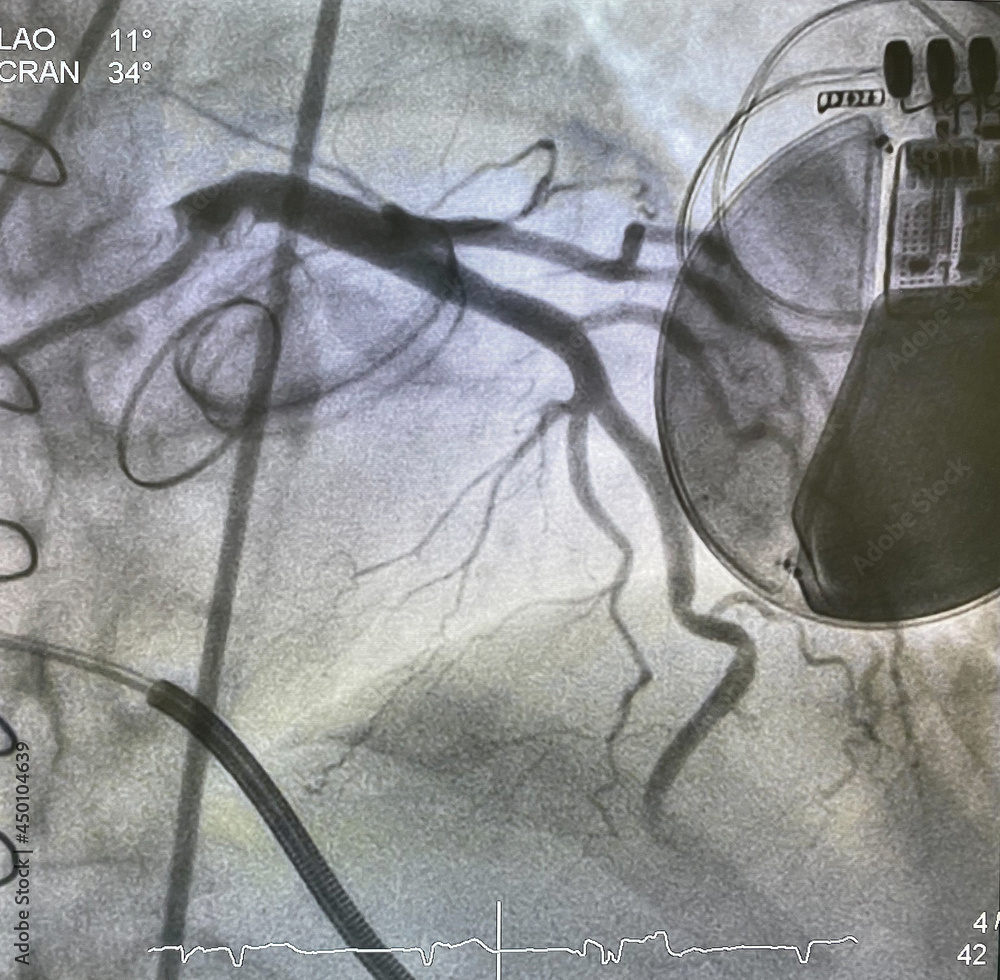

From stock.adobe.com

X ray image perform prosthetic heart valve, staples, steel suture and Prosthetic Valves X Ray The four valves of the heart may all be surgically replaced. prosthetic heart valves are common. The transthoracic approach is complemented with. the stenotic aortic valve is repaired by placing a prosthetic valve within the diseased valve. it is important to be familiar with the different types of cardiac valves and their radiographic appearances. chest radiographs. Prosthetic Valves X Ray.